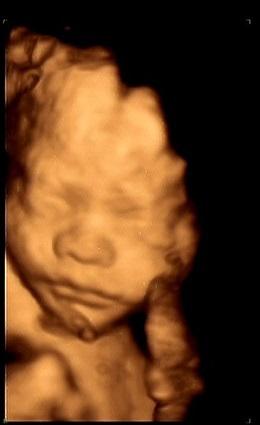

四维彩超即四维医学彩色超声成像技术。它 是在三维医学彩色超声成像的基础上加上第四维的时间矢量,能够实时显示三维立体图像。

说得更大众化一点,普通彩超显示的是图片,三维彩超显示的是静态立体图像,四维彩超显示的是动态立体图像。

胎儿四维彩超表面成像还可以直观地看到胎儿在母体内的活动状况,如:呼吸情况,运动情况等。